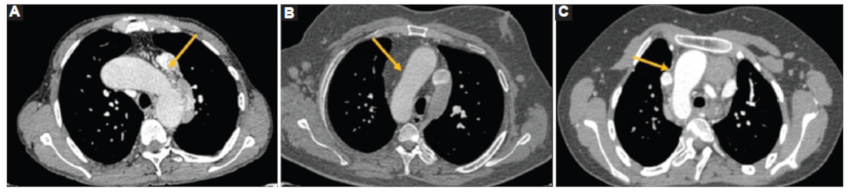

El retorno venoso pulmonar y sistémico puede ser anómalo y tiene una gran variedad de presentaciones. En el caso 1 se observó una anomalía parcial del retorno venoso pulmonar, la vena pulmonar superior derecha drenando a la aurícula derecha (Fig. 8A), asociado a un retorno venoso sistémico anómalo con la vena cava superior e inferior drenando ambas a la aurícula izquierda y estableciendo así un shunt pulmonar del retorno sistémico (Fig. 8 B y C). En el caso 3 se observaron dos venas cava superiores (derecha e izquierda); que drenan a sus respectivas arterias pulmonares (Fig. 8 D) determinando una alteración del retorno venoso sistémico.

El arco aórtico puede tener una posición variable tanto a derecha como a izquierda. En el caso 1 se observó a izquierda y en los casos 2 y 3 a la derecha (Fig. 9).